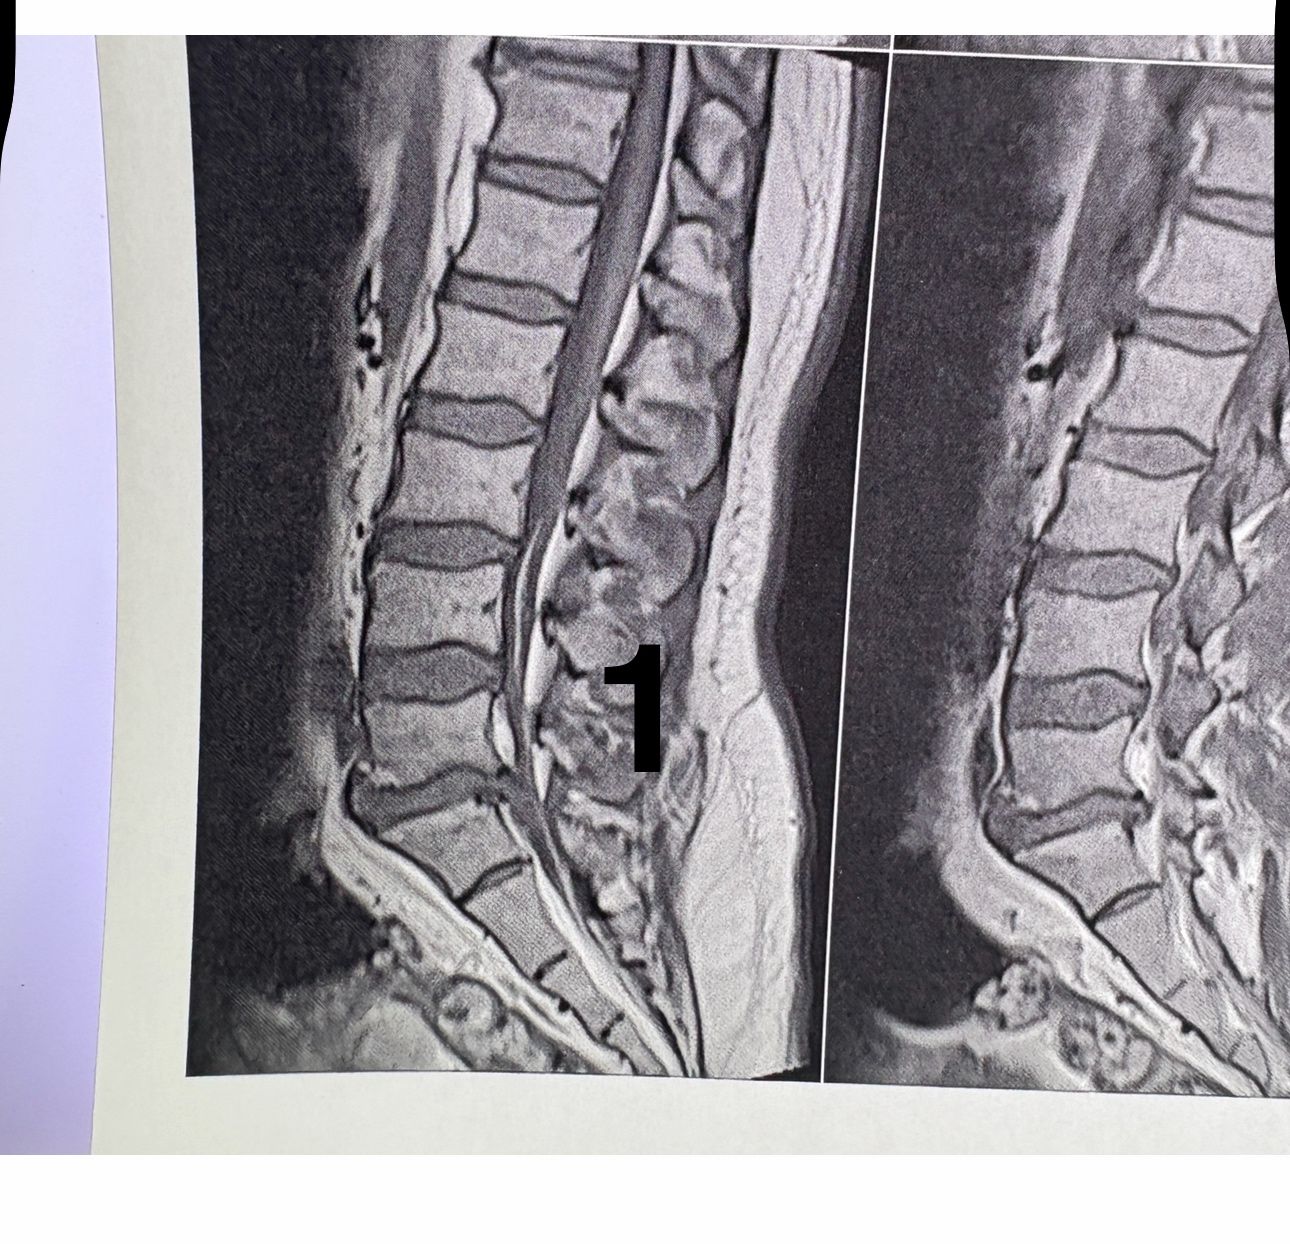

46 years old female patient presented to my clinic yesterday june 1/2025 with LBP and radicular L leg pain for several months which hasn’t responded to physio 2 neurosurgeons have visited her and didn’t suggest any surgery Neurological exam was unremarkable please see her mri/ emg/ncv and her huge tarlov cyst and possible L IVF L4-5 hyperbulge I ordered sacrum mri and ct scan and new emg/ncv and asked her with her sacral Ct scan and MRI first sees another two famous neurosurgeons and see if that large cyst is the reason for her pain if not i can work on her L4-S1 area Do you think her radicular pain can originate from her large cyst in sacrum? Do you consider surgery and removing her sacral cyst?